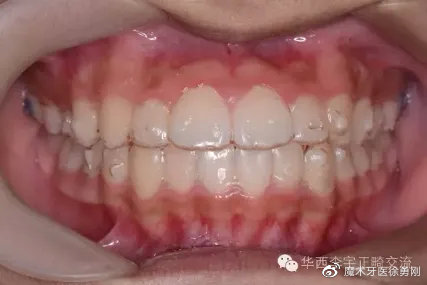

透明牙套佩戴在口内真实效果